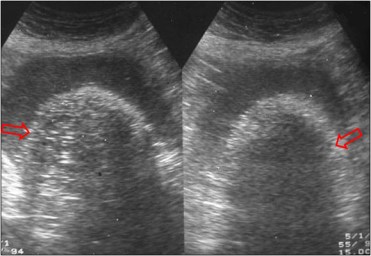

SIGNO DE LA PUNTA DEL ICEBERG

Signo específico de quiste dermoide ovárico visible en la ecografía tanto intravaginal como transabdominal. La presencia en una masa de pelo y grasa mezclados y las múltiples interfases que se producen, provocan una sombra acústica (flechas) que oscurece la parte más profunda de la masa.

En las fotografías se muestra un tumor dermoide en ecografía. se trata de la misma paciente del Signo de la pared.